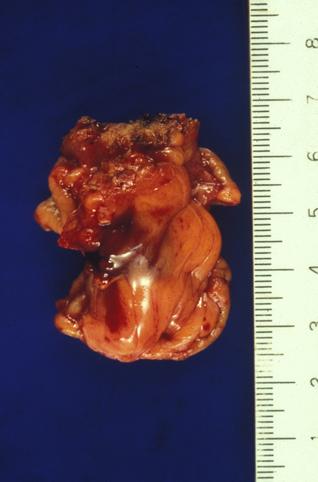

疾患(病理主体)の分類憩室/メッケル(Meckel)憩室

部位(臓器別)小腸/その他

検査方法マクロ

病変の最大径(ミリ)40以上